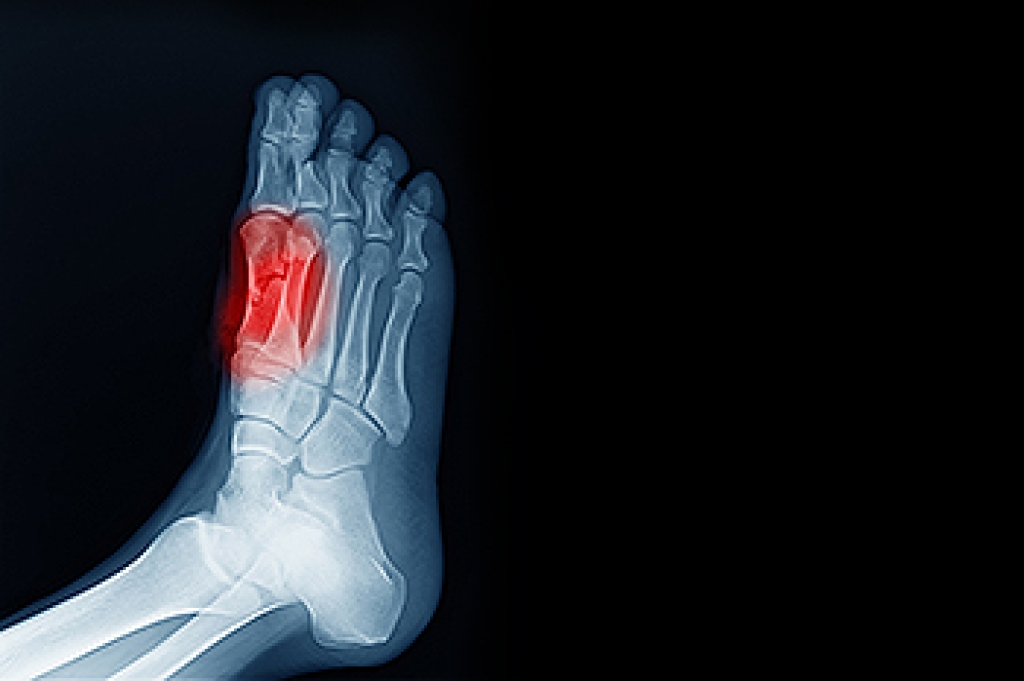

A podiatrist will treat the problematic areas of the feet, ankle or lower leg by prescribing the following:

- Surgery on lower extremity fractures